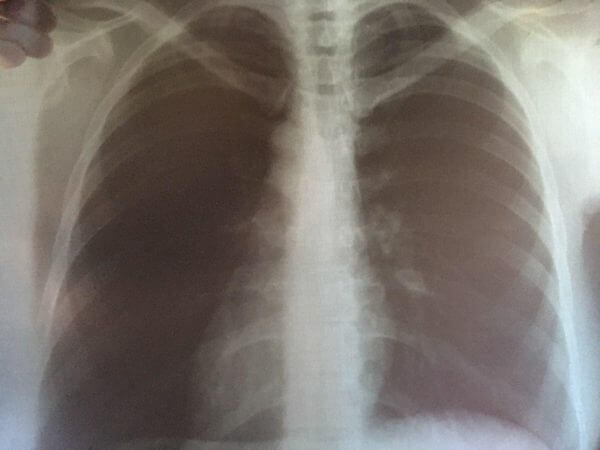

Как сообщает Орелстат со ссылкой на данные Управления Роспотребнадзора по Орловской области, в январе-апреле 2023 года по сравнению с аналогичным периодом прошлого года в регионе снизилась заболеваемость педикулезом – в 1,5 раза, туберкулезом – на 27,9 процента, сифилисом – на 20 процентов, острыми кишечными инфекциями – на 10,5 процента, острыми инфекциями верхних дыхательных путей – на 7,4 процента.

«Вместе с тем, число заболевших гриппом превысило уровень прошлого года в 76,2 раза, сальмонеллезными инфекциями – в 3 раза, — говорится в информационном отчете Орелстата. — Зарегистрировано 65 человек с болезнью, вызванной вирусом иммунодефицита человека и бессимптомным инфекционным статусом, вызванным вирусом иммунодефицита человека (ВИЧ), а также пять случаев заболевания клещевым боррелиозом».

Что касается новой коронавирусной инфекции COVID-19, то заболеваемость ею по сравнению с аналогичным периодом прошлого года снизилась в 8,6 раза. К слову, в оперативном прогнозе Главного управления МЧС России по региону, в целом санитарно-эпидемиологическая обстановка на территории Орловской области находится в норме. По информации Управления Роспотребнадзора, на территории региона зарегистрировано 140 616 подтвержденных случаев заболевания новой коронавирусной инфекцией, из них 138 364 человек выздоровели, а 1986 человек умерли с посмертным диагнозом COVID-19.